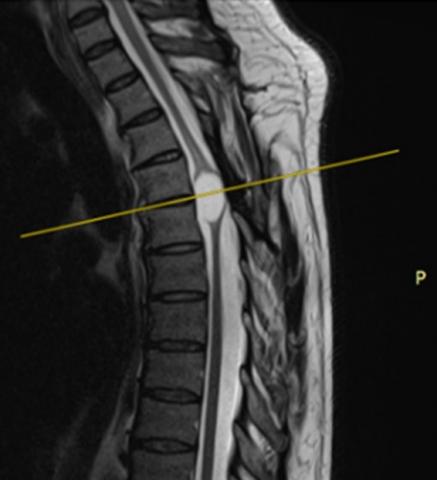

Experience in lumbar microdiscectomy at the Guillermo Almenara Irigoyen Hospital 2018 -2021

JOHN VARGAS U., RAÚL MARTÍNEZ S., EDUARDO LAOS P., ALFONSO BASURCO C.